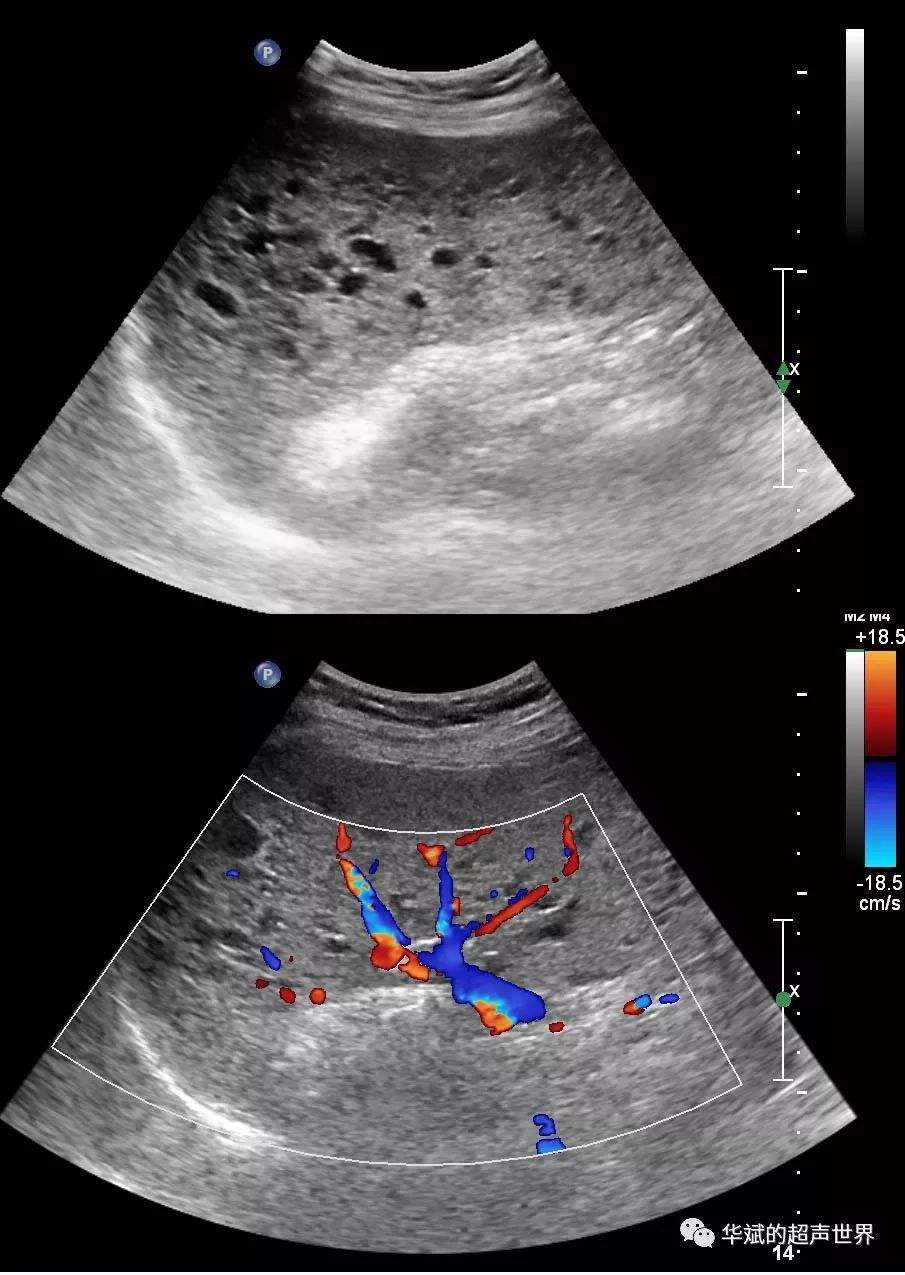

一、引起脾大原因有很多,比如说感染性脾大,各种急慢性感染和伤寒、副伤寒、黑热病、血吸虫病、痢疾、病毒性肝炎,败血症、晚期梅毒等,失血性脾肿大、班替氏综合征、肝硬化、慢性心力衰竭、至心源性肝硬化、慢性缩窄性心包炎,门静脉或脾静脉血栓形成。

二、增生性脾大,见于某些血液病,如白血病、溶血性贫血、恶性淋巴瘤、脾脏恶性肿瘤较罕见,脾脏囊肿、散播性红斑狼疮、皮肌炎、结节性多动脉炎、高雪氏病,因脾脏大多较复杂,除少是人的生理外,都应在医生的指导下寻病因,并要定期复查,脾大的原因和治疗的方法是互相相融的,知道了引起脾大的原因,那么就需要及时找到针对性的治疗方法,患者可以采用食疗来缓解或控制病情,也可以通过手术切除方法来治疗,这样可以起到立竿见影的效果。

脾大是否可以自行的恢复。最主要根据引起脾大原因决定。如果是感染,出现的感染性脾脏肿大,脾大多数为轻度,会伴有压痛感。在感染控制以后,短期内就可以恢复。如果因为肝硬化,而引起的脾脏肿大,脾脏自行恢复的可能性比较小。如果是血循环所导致的脾脏肿大,需要治疗原发病后,脾脏肿大才能有所恢复。

需要针对脾肿大的原因积极治疗,生理性脾肿大,常在体检时被发现,属于健康人群,没有不适症状,不需要治疗。血液系统疾病引起的脾肿大,需要针对血液疾病的病因进行治疗。门静脉高压导致的脾肿大,需要积极持续药物治疗,积极治疗原发病,降低门静脉压力,还可以介入手术治疗。感染性疾病引起的脾肿大,需要积极控制感染。